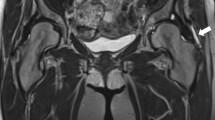

GTPS was diagnosed clinically; just a few patients had received magnetic resonance imaging of the hip joint. The included patients were referred to the radiotherapy centers from their general practitioners and orthopedic clinics for treatment.